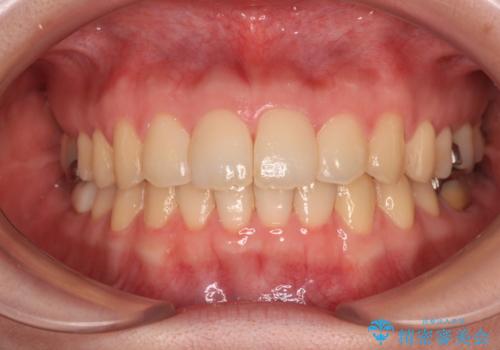

[前歯のねじれ・がたつきを治したい ]ワイヤーとマウスピースの併用矯正治療

![[前歯のねじれ・がたつきを治したい ]ワイヤーとマウスピースの併用矯正治療の症例 治療前](https://seimitsushinbi.jp/wp/wp-content/uploads/2023/11/IMG_0010-1-500x350.jpg?v=1699509973)

![[前歯のねじれ・がたつきを治したい ]ワイヤーとマウスピースの併用矯正治療の症例 治療後](https://seimitsushinbi.jp/wp/wp-content/uploads/2023/11/1c93ab7139a768f1f61b6dd35aac7324-500x350.jpg?v=1699510065)